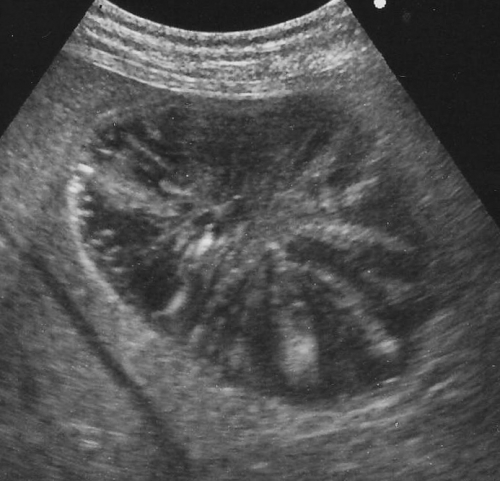

左下の写真が胆嚢粘液嚢腫の胆嚢の超音波検査のイメージです。本来は、画像上で真っ黒く抜けている円形の胆嚢の断面像に「キウイフルーツ」の切り口のように見えるようなパターンを生じるのが典型的ですが、その他に胆泥症との区別が難しいものなど、幾つかのバリエーションに富む異常を呈します。比較のために正常な胆嚢を右の写真を右写真に示します。

左写真のワンちゃんは胆嚢粘液嚢腫の診断後約1年で胆嚢破裂を起こして緊急手術となっています。